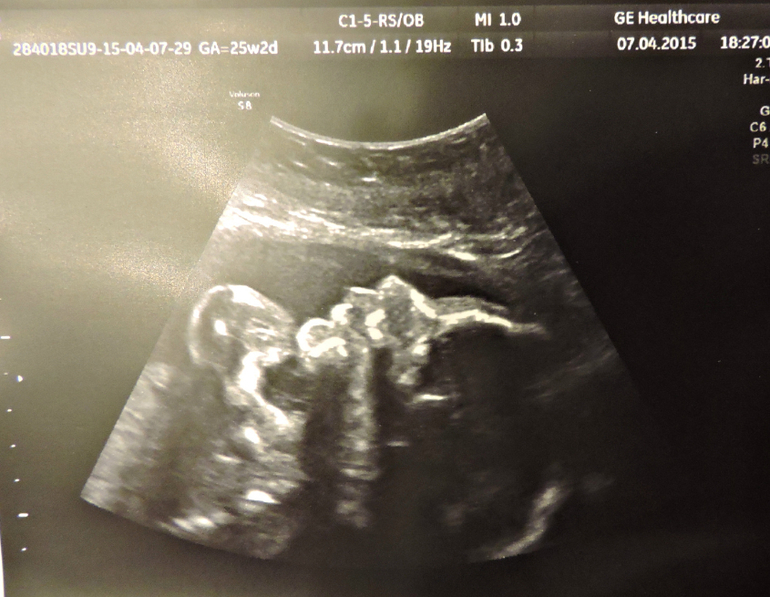

26 недель

Наши будни, наши неделькиСходила сегодня на УЗИ к Др.Озолине я просто в восторге , прекрасный врач , всё объяснила , всё показала , даже фотку дала и живот вытерла =))) и мы наконец то узнали , кто у нас будит МАЛЬЧУГАН =))) Вес его уже 780 гр , лежит головкой вниз , спинкой и попой с левой стороны живота и ножки наверху я прям пальчики видела на ножках , носик , губки и ещё у нас обвитие пуповины вокруг животика , но врач сказала , что обвитие лёгкое и ещё распутается , хотя меня мама родила с обвитием =) вообщем такой у нас был поход и теперь только к ней буду ходить =)